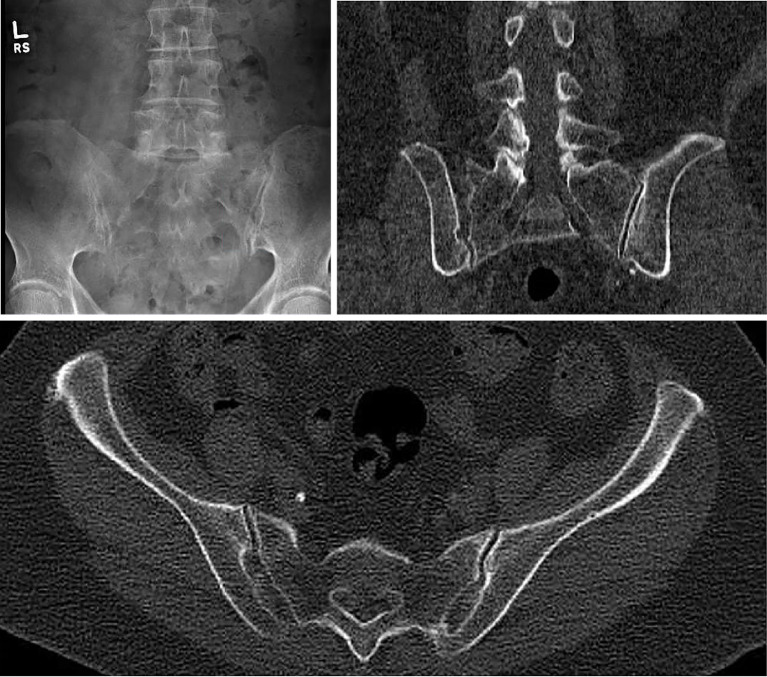

Background: Sacroiliac (SI) joint pain represents a common and often misdiagnosed source of low back and buttock pain. Importantly, SI joint pain can present with lower extremity radicular-type pain and closely mimic a herniated vertebral disc. During the physical exam, nearly all patients with back pain should be evaluated using provocative maneuvers that stress the SI joint. Diagnosis can be further supported with local anesthetic SI joint blocks. Plain radiographs and/or computed tomography (CT) imaging often demonstrate sacroiliac joint degeneration (e.g., joint space narrowing, vacuum phenomenon, osteophyte formation, sclerosis). Other diagnostic studies include magnetic resonance imaging (MRI) of the lumbar spine to evaluate the spinal column, spinal canal, and neural foramina and single photon emission computed tomography scan with CT (SPECT/CT) to identify foci with increased metabolic activity that could be pain generators.

Case description: We present the case of a 76-year-old woman with a 1-year history of progressive left-sided low back pain that progressed along an S1 radicular distribution and became debilitating, interfering with their activities of daily living. Specifically, the pain radiated along the left buttocks, down the posterior aspect of the leg, and into the heel. SPECT/CT demonstrated non-specific, symmetric radiotracer uptake within the bilateral SI joints. She had a positive response to two SI joint injections. The patient was ultimately treated with a SI joint fusion. This case raises questions regarding the sensitivity and specificity of SPECT/CT for SI joint pain. A minimally invasive surgery (MIS) lateral SI joint fusion using navigated and fenestrated screws can provide significant pain relief.